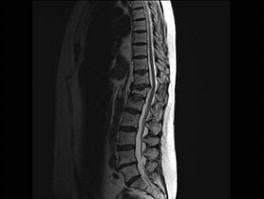

问题 男,65岁,背痛半月余,请结合影像学检查,选出最可能的诊断 ( )

选项 A、骨质疏松性椎体骨折 B、脊椎退行性变 C、脊柱转移瘤 D、化脓性脊柱炎 E、脊椎结核

答案 A